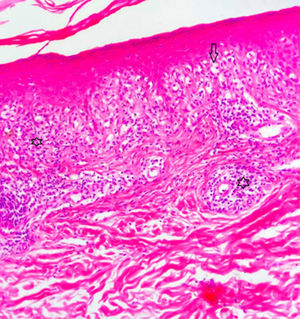

Una mujer de 42 años de edad acudió con lesiones pruriginosas en el cuerpo en el curso de 5 meses. La exploración dermatológica reveló amplias zonas de pápulas y placas liquenoides de tonalidad de eritematosa a púrpura en el tronco y las extremidades (fig. 1 a-c). La mucosa oral y genital, así como las uñas, eran normales. La paciente manifestó que 10 días antes de la aparición de las lesiones cutáneas se le había realizado una PCR confirmatoria de infección por COVID-19. No fue hospitalizada, pero recibió favipiravir y tratamiento analgésico para COVID-19. La información aportada por la paciente con relación a la COVID-19 fue también confirmada mediante la consulta de la base de datos disponible en nuestro país. La infección remitió en un plazo de 5 días, empezando a aparecer las lesiones cutáneas poco después. Sin embargo, la paciente no consultó a ningún médico durante este proceso, esperando que las lesiones desaparecieran por sí mismas, por lo que la relación entre la COVID-19 y las lesiones cutáneas no fue documentada en este periodo, y de ahí el punto débil del documento. Se estableció diagnóstico diferencial de liquen plano, erupción liquenoide por fármacos, PLC, pitiriasis rosada atípica y prurigo. El examen histopatológico reveló la existencia de hiperqueratosis, acantosis irregular, espongiosis focal y exocitosis linfocitaria en la epidermis, e infiltrado linfomonocítico en forma de banda y melanófagos en la dermis superficial (fig. 2). Se estableció el diagnóstico de PLC con los hallazgos clínicos e histopatológicos actuales. Se trató a la paciente con doxiciclina oral, corticosteroides tópicos y emolientes. Las lesiones no mejoraron tras un mes de tratamiento con doxiciclina, iniciando la paciente sesiones de UVB de banda estrecha.